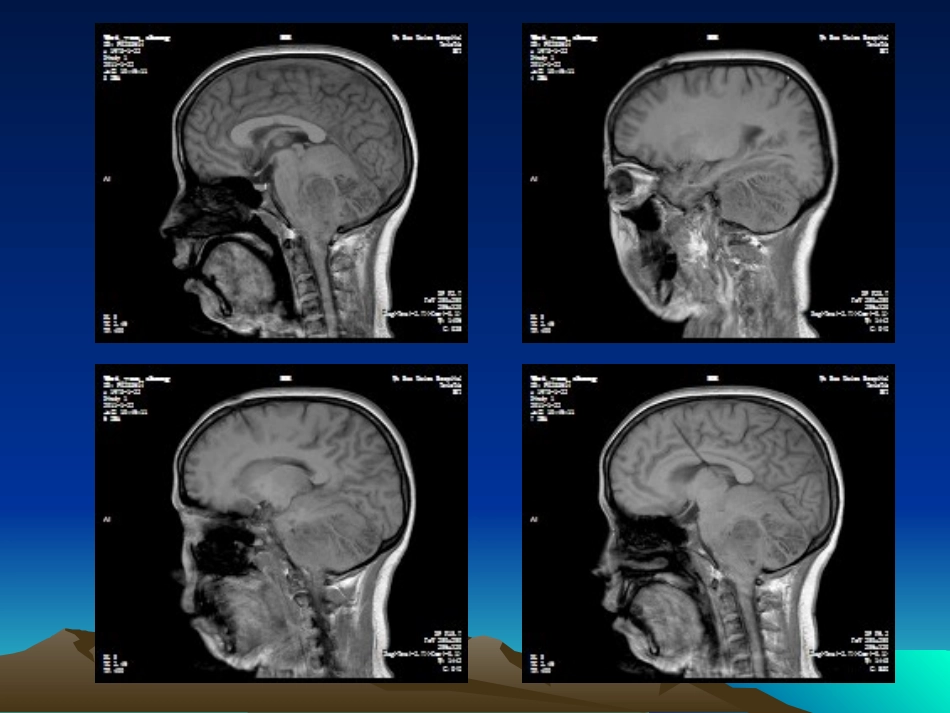

CASECASE男性,33岁,行走不稳三天小脑发育不良性节细胞瘤•罕见的小脑良性占位性病变•起自小脑皮层、缓慢进展•WHO分类:神经元和混合神经元、神经胶质肿瘤,Ⅰ级良性肿瘤•性质、发病机制和遗传学改变尚不完全清楚,是原发肿瘤、发育畸形或是错构瘤性病变仍有争论•发病年龄从新生儿至74岁不等,以10~30岁者多见,平均为34岁;无性别差异•小脑半球和中线均可发生•常见症状体征:第四脑室或中脑导水管受压引起梗阻性脑积水所致的颅压增高和后颅窝占位表现•40%伴有Cowden综合征病理特征病理特征•①弥漫或局限性小脑皮质增生,累及一侧或两侧小脑半球甚至小脑蚓部,病变侧中央白质一定程度的减少;•②大体见分子层苍白、增厚,间有有髓纤维;浦肯野细胞层缺如,颗粒细胞层增宽并含有大量异常颗粒细胞,其轴突伸入分子层;•③常见钙质沉积于分子层的毛细血管、微血管壁。